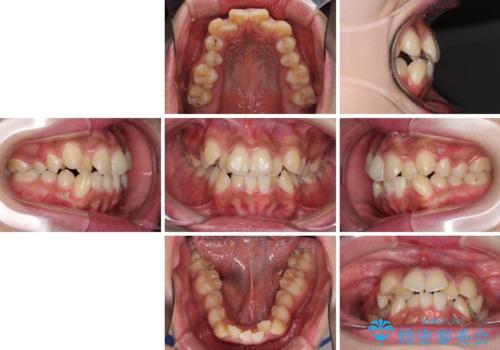

- 八重歯と上下前歯のでこぼこを気にして来院された患者様です。

上下前歯部叢生のスペース獲得のため、上下顎左右小臼歯各1歯(計4本)と全ての親知らずを抜歯して、矯正治療を行うこととしました。

上下の正中位置が大きくずれていたため、治療期間の長期化や正中が合わないまま終了することが予想されましたが、思っていた以上にスムーズに歯が移動し、満足いただける仕上がりとなりました。